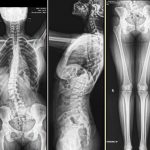

Radiología / Espinograma